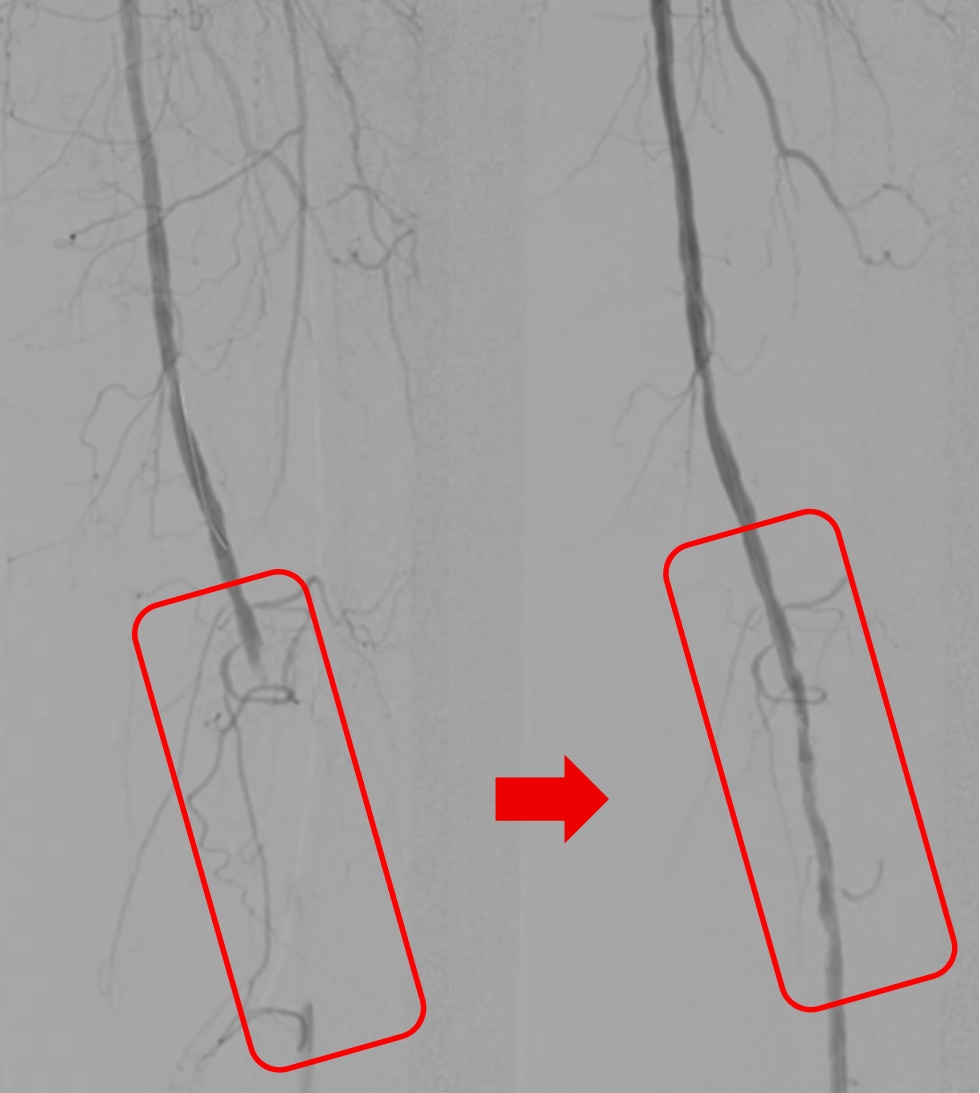

血栓的形成堪称“血管堵车事件”堵住冠状动脉可能导致心梗,堵住大脑动脉可能导致脑梗死,住下肢动脉(见下图)可能导致坏疽,堵塞肺动脉起肺栓塞……

红框内的下肢动脉血栓被清除

不同的血栓治疗方式也是不同的[4]。没有明显临床症状的血栓大部分可以保守治疗,通过抗血小板、抗凝等活血的手段治疗和延缓血栓的进展。